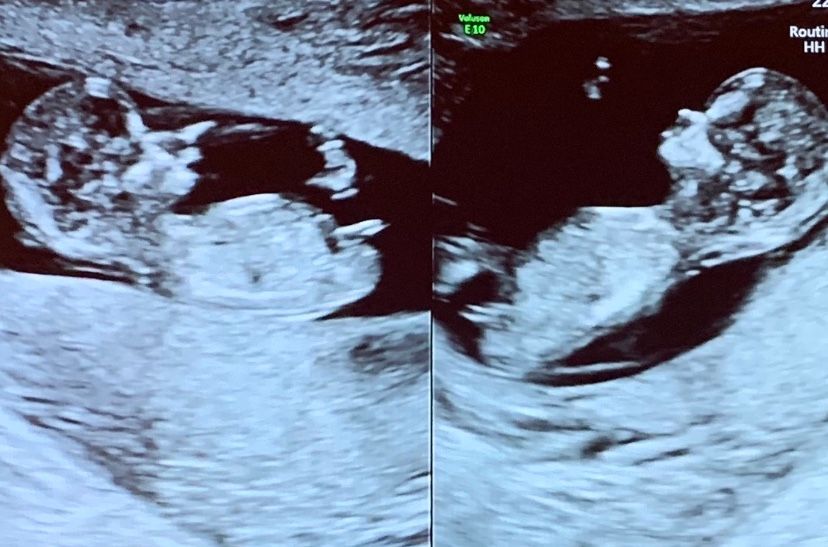

На первом скрининге сказали, что один из малышей почти точно мальчик. Я «изучила» сравнила фото узи малышей в инете на таких же сроках и положение их «шпыньков»)) и очень похоже на девочек.

Я как-то плохо вижу на фото что где). Но мне на 1м скриннинге врач сразу сказал, что 2 девицы и показал половые бугорки- они почти параллельно позвоночнику были. У мальчиков, я так поняла, они вверх

Мне кажется либо оба мальчика, либо слева девочка, а справа мальчик, но я так себе диагност😁

Слева вроде девочка, справа мальчик 😊 мне так кажется) тоже насмотрелась на кучу шпыньков неделю назад 😄

Наталья, в том и дело, что сказали слева мальчик)) а мне кажется, что вообще две девочки